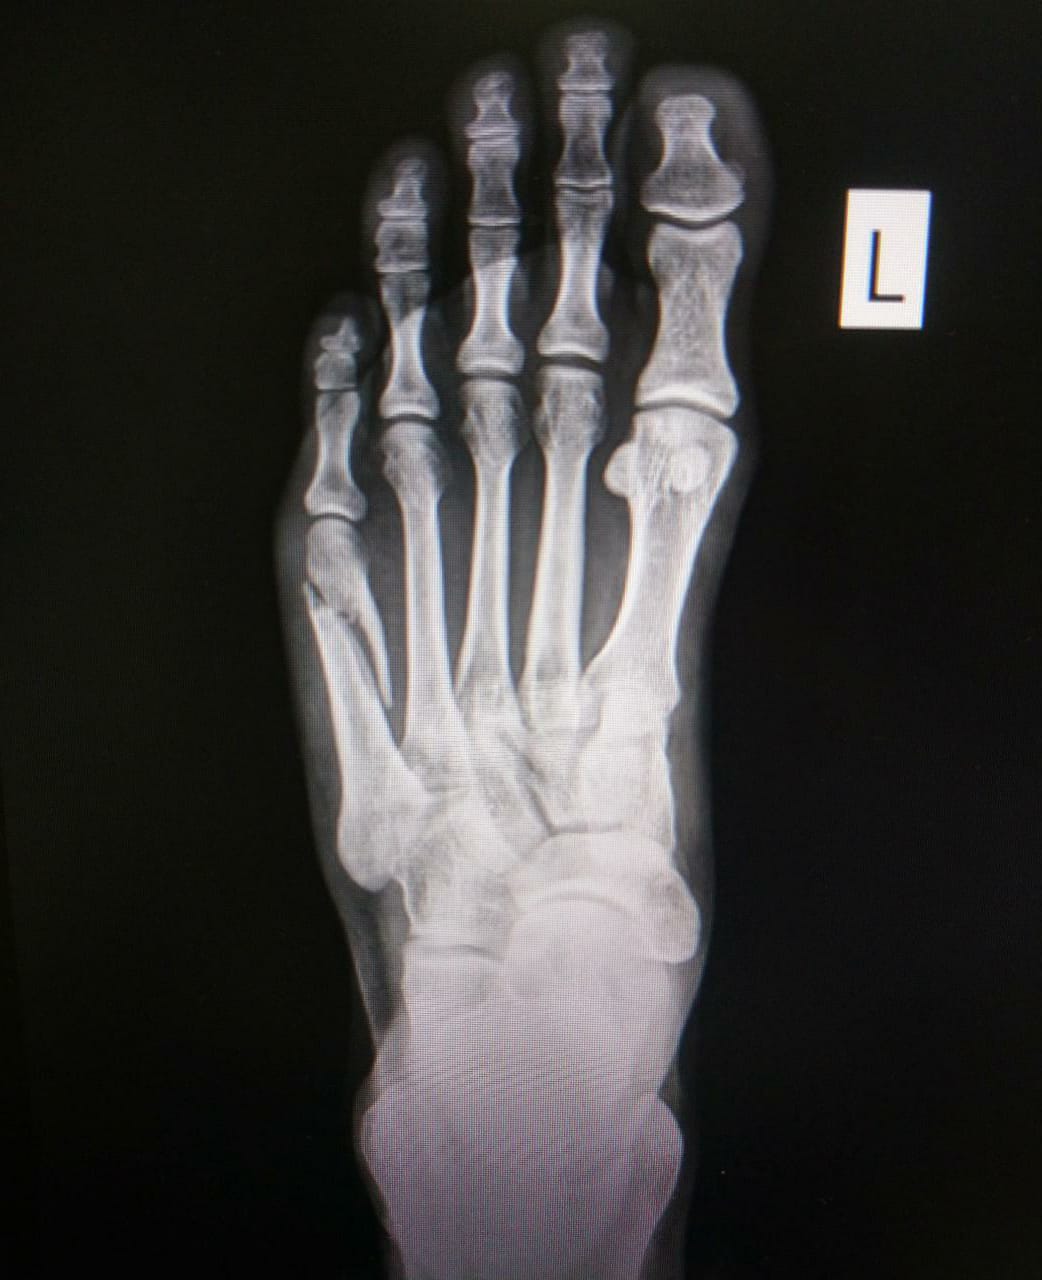

Плюсневые кости находятся в передней части стопы и соединяются с костями предплюсны сзади и фалангами пальцев спереди. В анатомии выделяют пять плюсневых костей, которые пронумерованы от I до V, начиная с большого пальца. Каждая из них состоит из трех частей: головки, тела и корпуса. Головка плюсневой кости выступает в виде выпуклой части, которая контактирует с фалангами пальцев, а основание — крепится к предплюсне.

Расположение плюсневых костей прямо влияет на biomechanics стопы, а также на равномерность распределения нагрузки. Каждая кость занимает своё место в виде своеобразной дуги, что обеспечивает оптимальный баланс и амортизацию.

Анатомические особенности каждой плюсневой кости

| Нумерация | Кость | Описание | Особенности |

|---|---|---|---|

| I | Большая плюсневая кость | Самая длинная и мощная из плюсневых, соединяется с первым пальцем | Особая форма головки для пальцев с большим движением |

| II | Вторая плюсневая кость | Находится рядом с первой, участвует в образовании поперечной арки | Меньше, чем I, с более гладкой поверхностью |

| III | Третья плюсневая кость | Центральная и самая короткая из первых трех, помогает в формировании средней части стопы | Особенности строения для поддержки уравновешенности |

| IV | Четвертая плюсневая кость | Менее развитая и короткая, участвует в формировании боковой части стопы | Может иметь вариации в строении у разных людей |

| V | Маленькая плюсневая кость | Самая короткая и узкая, расположена на внешней стороне стопы | Обеспечивает боковую стабилизацию и подходит для разнообразных движений |

- Рентгенография — наиболее доступное и информативное исследование